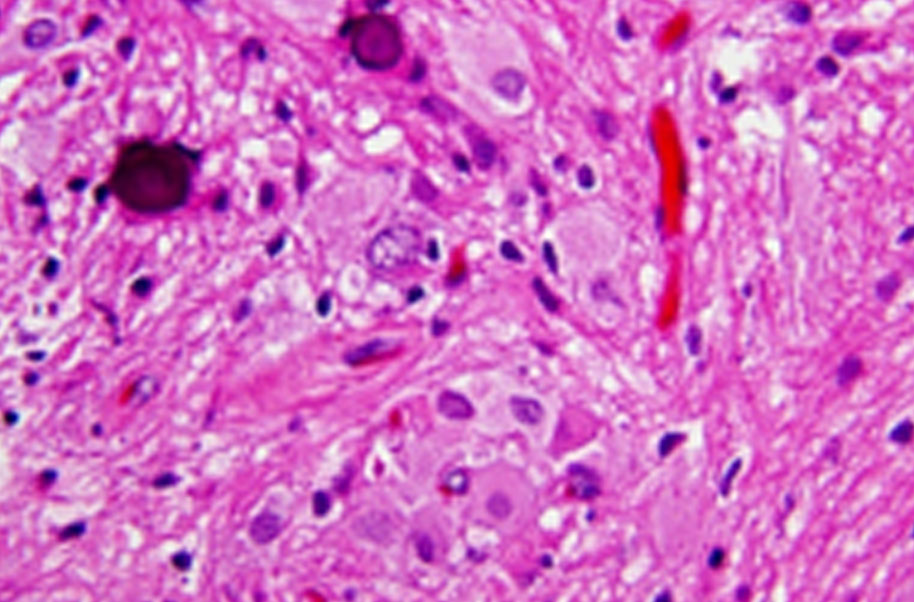

Subependymal giant cell astrocytoma (sega, sgca, or sgct) is a low-grade astrocytic brain tumor (astrocytoma) that arises within the ventricles of the brain. It is most commonly associated with tuberous sclerosis complex (tsc).

Subependymal giant cell astrocytomas (sgcas or alternatively segas) are benign tumours (who grade i), seen almost exclusively in young patients with tuberous sclerosis. They can be either asymptomatic or symptomaticdue obstructive hydrocephalus, surgery treatment is oftencurative.